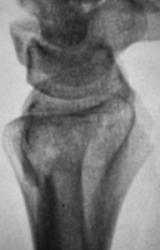

Пациент направлен врачом общей практики (ВОП) на рентгенографию лучезапястного сустава с диагнозом "Перелом?". Произведено стандартное исследование лучезапястного сустава. Выявлен перелом лучевой кости в типичном месте почти без смещения отломков, перелом локтевой кости в области основания шиловидного отростка с незначительным смещением отломков по ширине. Возникает подозрение на разрыв дистального луче-локтевого сочленения. Ваше мнение коллеги?